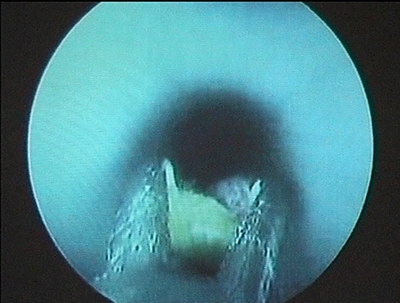

Камни подвергнуты трипсии ультразвуковым методом. Удалено

9 конкрементов монолитом, остальные литолапаксией. ЛМС почки

интактен. Контрольная нефропиелоскопия, рентгеноскопия –

резидуальных конкрементов не выявлено. Собирательная система

дренирована нефростомой типа фоллей № 20 F. Дренаж фиксирован

к коже викрилом 2/0. Асептическая повязка. Макрогематурия

минимальная.